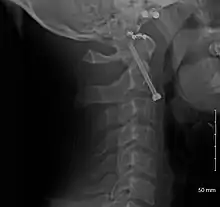

A fracture of the base of the dens as seen on plain X-ray

A fracture of the base of the dens as seen on CT

Type 2 dens fracture